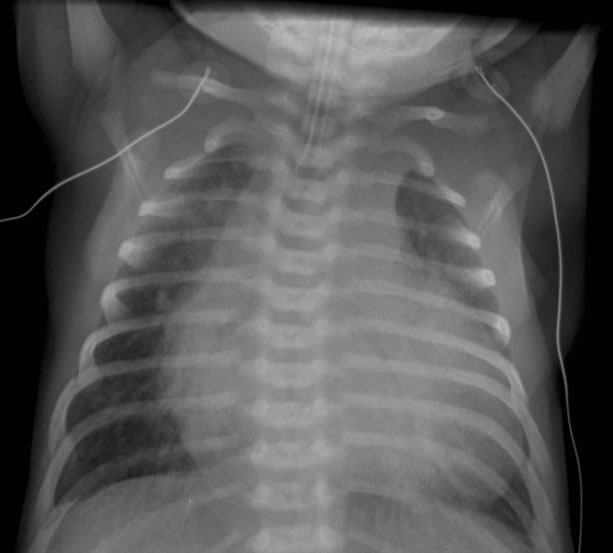

Post-intubation CXR for the case found here:

(CXR source: http://www.adhb.govt.nz/newborn/TeachingResources/Radiology/CXR/OtherCHF/NonstructuralCHF.jpg)